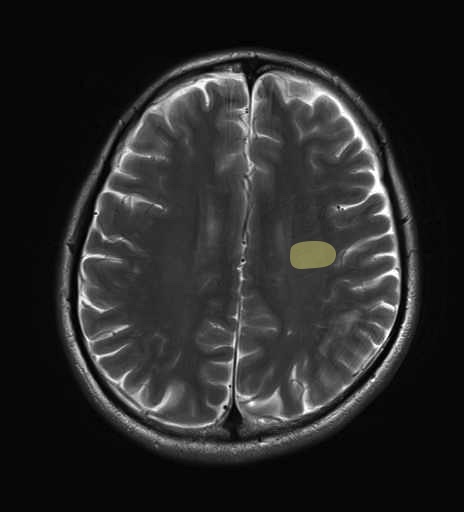

錐体路・皮質脊髄路のMRI画像解剖

運動系 錐体路系に色を付けました。

■皮質脊髄路(いわゆる錐体路):一次運動野から脊髄遠隔の下位運動ニューロン細胞体まで